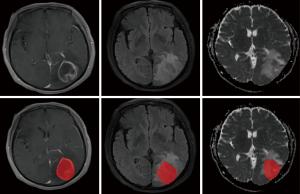

Tumour region of interest (ROI) segmentation

Image segmentation was performed using ITK-SNAP software. To ensure the accuracy of ROI delineation, two radiologists with 10 and 15 years of experience manually segmented the images independently in a blinded manner. The final ROI was determined as the overlapping area of the segmentation results from the two radiologists and was validated by a senior radiologist with 20 years of experience. In order to evaluate the stability and repeatability of radiomics features, inter-rater analysis was performed based on the segmentation results of the first two radiologists, and the inter-group correlation coefficient (ICC) was used as a measure. The radiomics flow chart is shown in Figures 2,3.